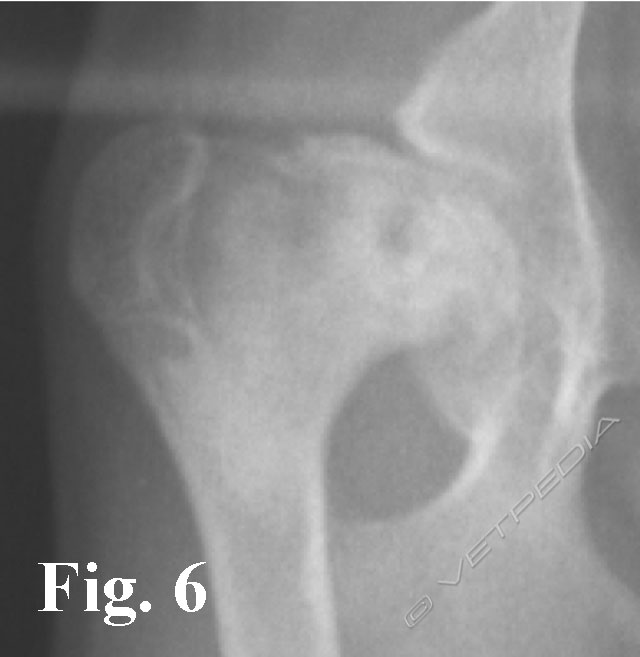

{{/_source.additionalInfo}}La necrosi asettica della testa del femore è anche denominata malattia di Legg Calvè Perthes e necrosi avascolare della testa del femore. Si tratta di un'affezione ortopedica coinvolgente l’articolazione coxofemorale di cani di razza toy o di piccola taglia durante il periodo dell’accrescimento, ad interessamento più frequentemente monola